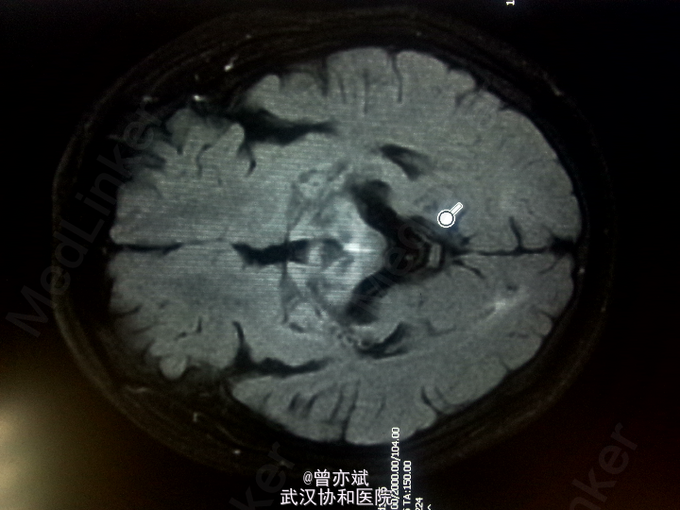

查体:T 36.4℃,P 77次/分,R 20次/分,BP 110/70mmHg。神志清楚,查体合作,皮肤及全身浅表淋巴结未及肿大,心肺腹未及明显异常,双下肢无水肿,生理反射存在,病理反射未引出。 专科查体:神清,吐词不清,语速减慢。双侧角膜可见K-F环,颅神经(-),四肢肌力正常,肌张力减低,左上肢不自主运动,姿势性震颤明显,腱反射对称性活跃,病理征未引出。感觉系统无异常。左手指鼻试验不准。Kernig征阴性。 辅助检查:血常规、尿常规、大便常规、大生化、ENA、ANCA、甲功五项、类风湿三项均阴性,铜蓝蛋白小于20mg/L(正常值220-580mg/L),叶酸、VitB12均正常。MRI平扫+增强 双侧基底节、丘脑、中脑及桥脑、双侧齿状核稍长T1稍高FLAIR信号及双侧苍白球、壳核及黑质信号改变,结合病史考虑肝豆状核变性;脑萎缩,尤以小脑桥脑明显。